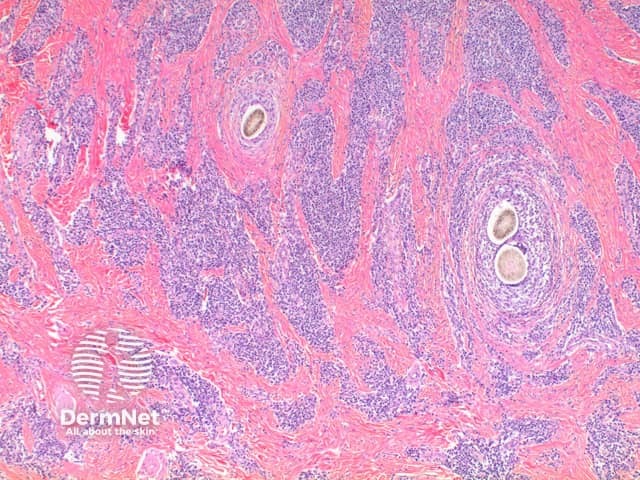

Low power view exhibits a dense superficial and deep inflammatory process with dermal scarring and follicular disruption (Figure 1). There may be variable degrees of overlying scale crust with tufted hair follicles evident as multiple hair shafts within widened follicular infundibulae (Figures 1 and 2). In the dermis are disrupted hair follicles with scattered naked hair shafts seen within a fibrotic dermis (Figures 2 and 3). There is a dense lymphoplasmacytic infiltrate with scattered neutrophils (Figure 4).

Figure 2